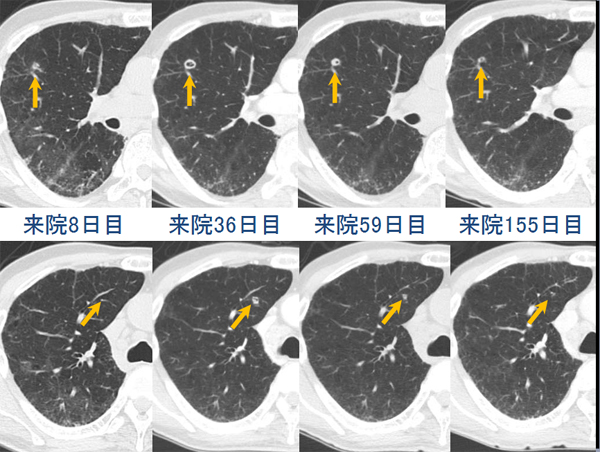

両肺に数少ないが多発結節(小葉との関係は判断困難)の出現、出現速度は速く、増大経過(LVFX抵抗性)

2010.05.27 抗生剤( LVFX )投与開始後 解熱なし

2010.06.2) 初診から5週後

増大したものの一部に空洞形成、左上区の最大のものの空洞内には同心円状・索状構造がみられる